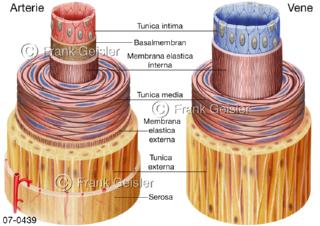

Bilder zu Herz, ein muskuläres Hohlorgan, das den menschlichen Körper durch rhythmische Kontraktionen mit Blut versorgt und dadurch die Durchblutung der Organe sichert, das Kreislaufsystem zeigt den Transport von arteriellem sowie venösem Blut durch das kardiovaskuläre System (Herz-Kreislauf-System), bestehend aus Blutgefäßen, Lymphgefäßen und dem Herz